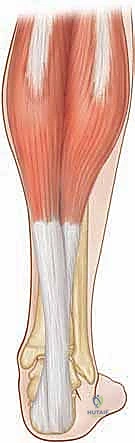

العضلة النعلية (Soleus Muscle):

تقع بشكل عميق تحت العضلة التوأمية، وتنشأ من الجانب الخلفي لعظمي الساق (الظنبوب) والشظية (تحت مفصل الركبة). تنضم أليافها الوترية إلى وتر أخيل في نقطة أبعد (أقرب للكاحل)، وتسهم بشكل كبير في السُمك والقوة الإجمالية للوتر. العضلة النعلية هي "عضلة ذات مفصل واحد"، حيث تقتصر وظيفتها على تحريك مفصل الكاحل فقط.